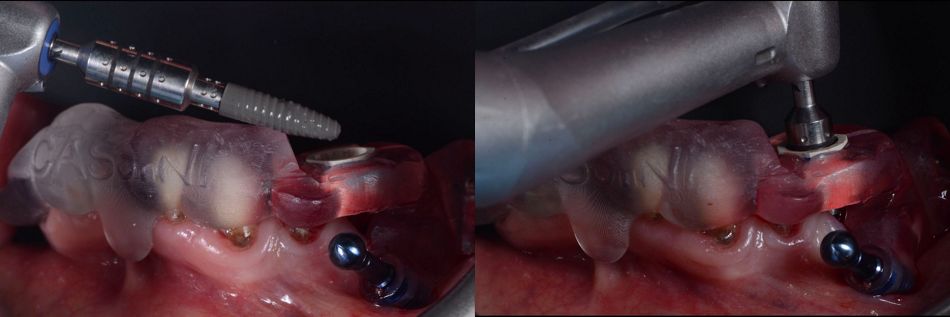

The lower jaw was then treated under local anesthesia. Prior to the surgical phase, the prosthesis was removed, followed by the extraction of teeth #34 and #43 (Figs. 43,44).

For the lower jaw, implants were placed using a surgical guide following the planned drilling protocol (Figs. 45,46).

Implant placement was performed using Straumann® BLC™ implants: a Ø 3.3 mm Regular Base, 12 mm SLActive® implant at site 34 and a Ø 3.3 mm Regular Base, 10 mm SLActive® implant at site 43 (Fig. 47).

Fig. 47